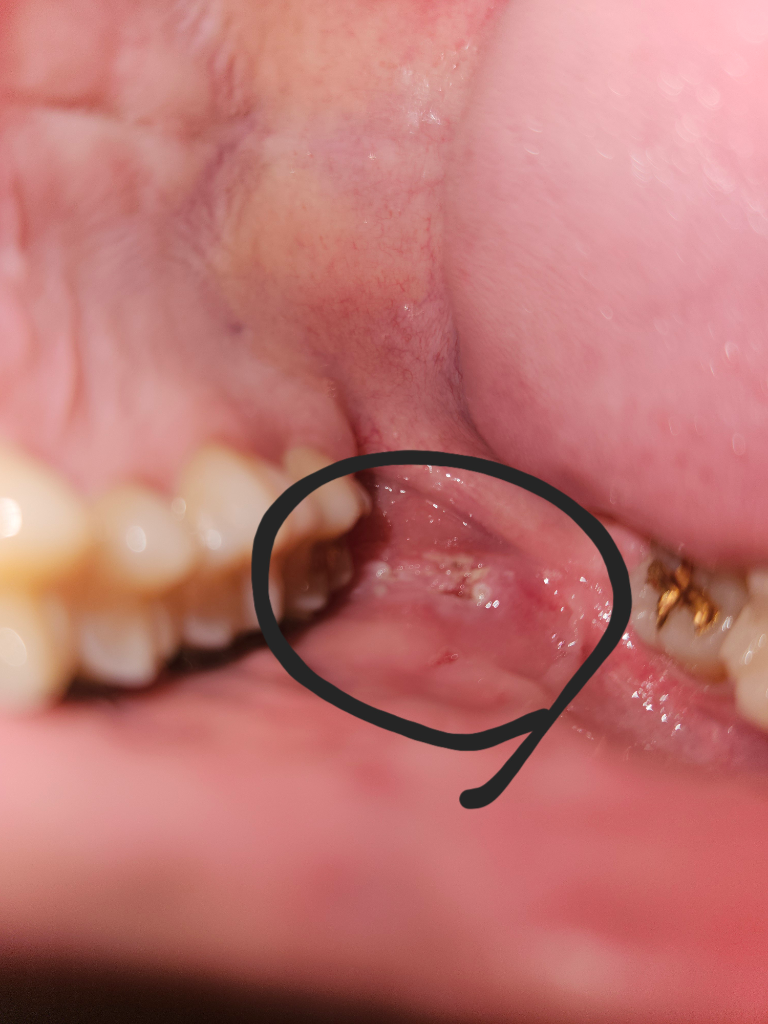

현재 치아 교정 중입니다. 두 달 전 식사를 하던 중 교정기 철사가 왼쪽 볼을 찌르며 볼살에 낀적이 있는데 그때는 상처가 없었던것같고 후에 치과 방문 후 철사가 볼을 찌르지 않도록 조치 하였습니다. 그 후 따로 아픈적은 없었던거같은데 대략 2주 전 그때 찔렸던 왼쪽 볼에 상처가 났으며 상처 부위에 음식을 씹으며 치아가 닿거나 양치를 하는 등 무언가 닿게 되면 아프고 무언가 닿지 않으면 별 다른 느낌이 없습니다. 그냥 단순히 교정기가 쓸려 난 상처인가요? 아니면 다른 병이나 그런게 있는 건가요 병원은 이번주 방문이 힘들어 다음주 토요일 27일에 치과 방문이 예약되어 있어 그때 방문할까 합니다.아래 사진 첨부합니다.

입안에 염증이 생긴 것으로 보이며, 이 경우 소독을 위해 헥사메딘 가글액으로 가글하고, 구내염 연고 사용을 하며 상태를 지켜보길 권합니다.

양상은 외상성궤양이고 위치상 교정 철사의 찔림으로 그런것 같습니다 구강내 적용가능한 연고를 바르면 도움이 됩니다